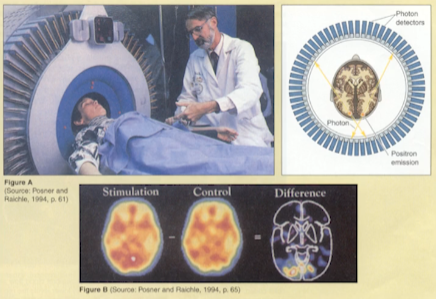

- 研究大脑的工具

图1-8 - 核磁共振

- 正子断层扫描(PET Scan)

- 脑造影技术

你想象和你在做会活化同样的神经回路,所以沙盘演练有用、杀鸡儆猴也是有根据的。